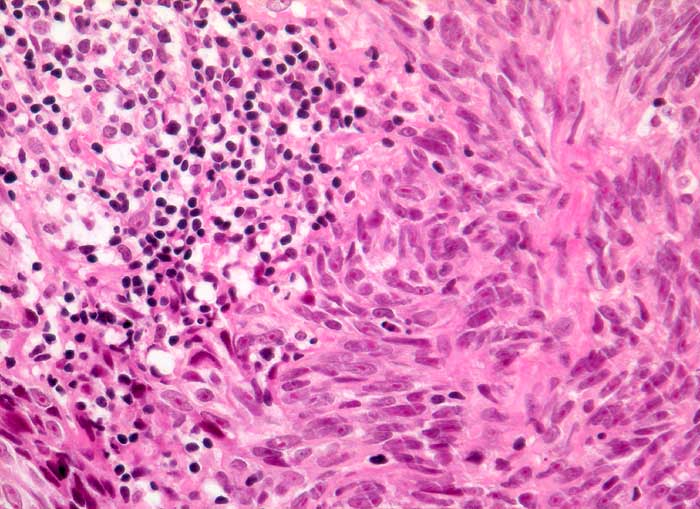

PathoPic – image database / PathoPic ID 5578 - Malignes Melanom

Malignes Melanom

Lymphknoten, Axilla

Links im Bild Reste des Lymphknotens. Zu kurzen Faszikeln angeordnete Tumorzellen mit spindeligen Kernen und auffallenden eosinophilen Nukleolen. Kein Pigmentnachweis.

Seit zwei Monaten zunehmende axilläre Lymphknotenschwellung.

Histologie

320